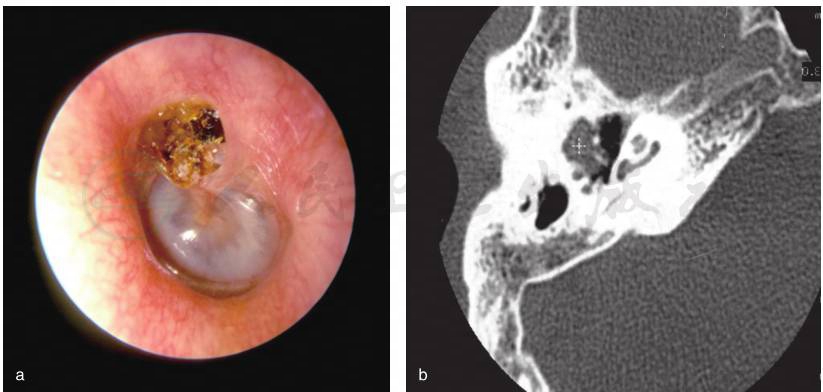

是由位于松弛部、紧张部或者两者并存的内陷袋(当内陷袋失去自洁能力、角化碎片开始堆积的时候,内陷袋逐渐发展成为后天性胆脂瘤)以及穿过基底膜的基底细胞侵犯发展而来,可能继发于中耳压力调节功能紊乱,也可能继发于由以前的中耳炎、创伤、医源性因素导致的鼓膜穿孔。因此,将后天性胆脂瘤分为内陷袋性胆脂瘤和非内陷袋性胆脂瘤。内陷袋性胆脂瘤进一步分为松弛部胆脂瘤(上鼓室胆脂瘤)、紧张部胆脂瘤、松弛部和紧张部皆有的胆脂瘤;非内陷袋性胆脂瘤进一步分为继发于鼓膜穿孔的胆脂瘤(后天继发性胆脂瘤)、继发于创伤或者耳科手术的胆脂瘤(图2)。

图2 后天性松弛部内陷袋性胆脂瘤(左耳)

a.鼓膜松弛部内陷囊袋,内有胆脂瘤上皮堆积,表面痂皮覆盖;b.颞骨CT见听骨链外侧团块状软组织影,盾板骨质破坏吸收,骨质周缘光滑锐利